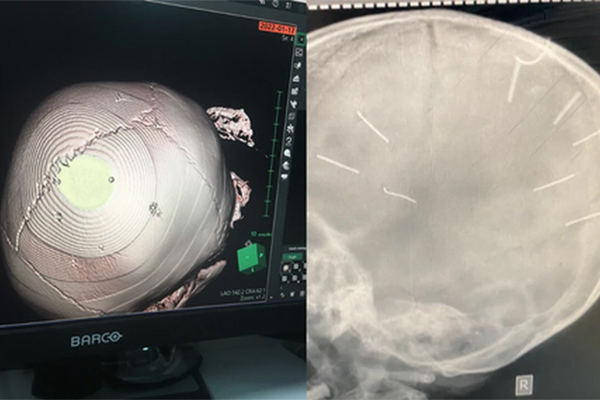

Trước đó, như Dân trí đưa tin, cháu Đ.N.A (3 tuổi) tại Thạch Thất, Hà Nội được đưa đến cấp cứu tại Bệnh viện đa khoa Thạch Thất khi trong đầu có 9 vết đinh, cháu bé ngay lập tức được chuyển lên tuyến trên, Bệnh viện đa khoa Xanh Pôn, Hà Nội để cấp cứu, hồi sức tích cực.